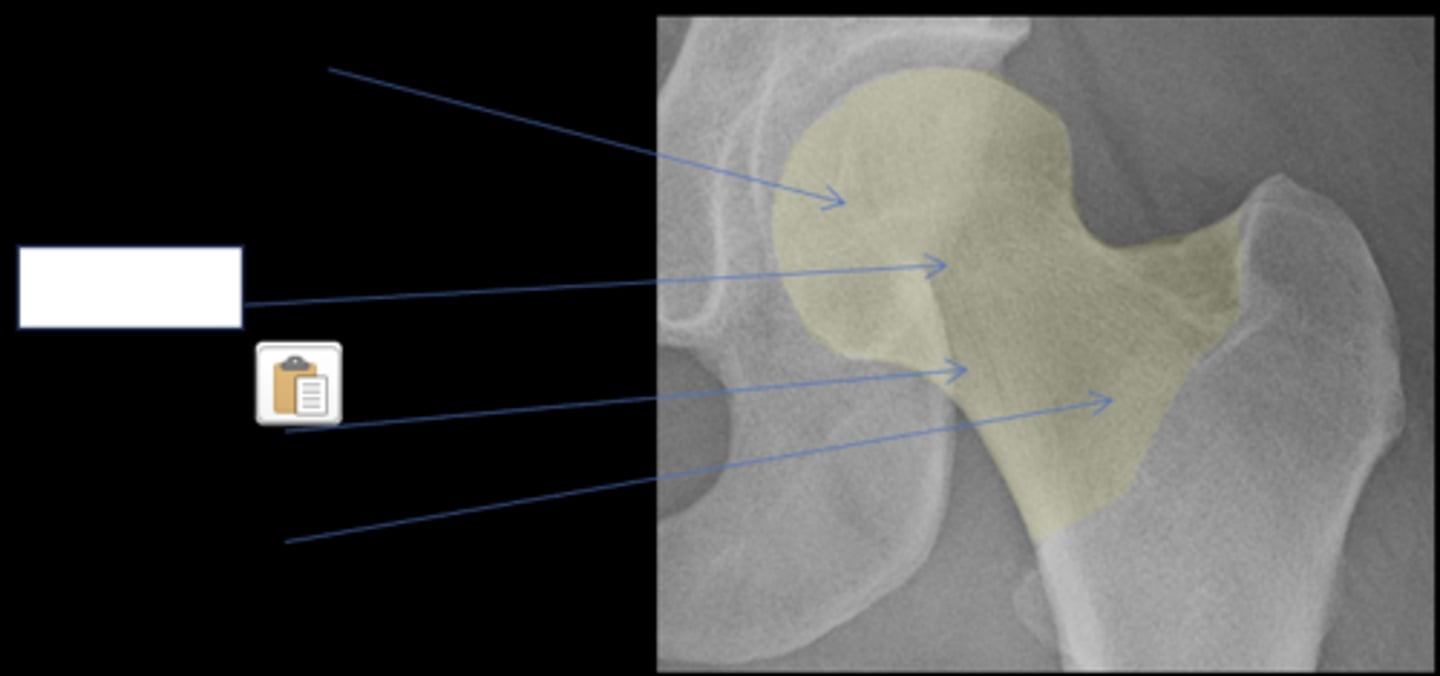

Femoral head

ID anatomy

<p>ID anatomy</p>

Subcapital

Mid-cervical

Basicervical